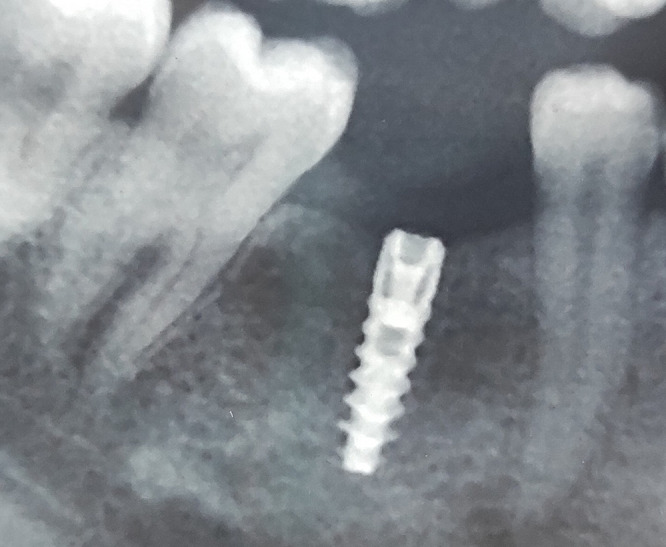

Patients and methods: This case report highlights a case of early bone loss and implant failure possibly due to compression necrosis. Clinical data, photographs, radiographs, blood examination report and histology were presented to document the early failure of an implant placed in the mandibular left posterior region of a 33-year-old female patient.

Results: Radiograph taken six weeks after implant placement showed severe angular defect. Therefore, the implant was surgically removed. Histological examination of the area showed bony trabeculae with an absence of osteoblastic riming, suggestive of necrotic bone.